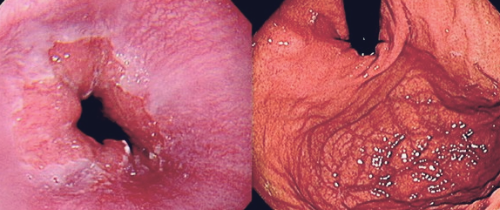

역류성 식도염으로 속이 쓰릴 때 흉골 뒤쪽의 가슴에서 타는 듯한 느낌이 들며, 위의 구덩이에서 시작해 목 뒤 쪽으로 빠르게 상승합니다. 이 통증은 목과 팔 뼈의 중심부로 이어질 수 있는데, 식도염이 의심되면 상부 소화관 내시경 검사를 받아야 하는 이유입니다.

역류성 식도염을 치료하는 방법은 역류성 식도염 증상정도에 따라 달라질 수 있습니다. 우선 위에서 설명한 예방 수칙을 실천하는 등 생활 습관을 교정하는 것이 가장 도움이 됩니다. 다른 치료법으로는 내시경을 사용하여 하부 위식도 괄약근을 강화하여 역류를 줄이는 방법이 있으며, 이는 의사의 재량에 따라 시행됩니다. 위산 억제제, 위산 중화제, 위장 이완제와 같은 약물을 사용하여 증상을 완화할 수도 있으며, 의사가 처방할 수 있습니다.